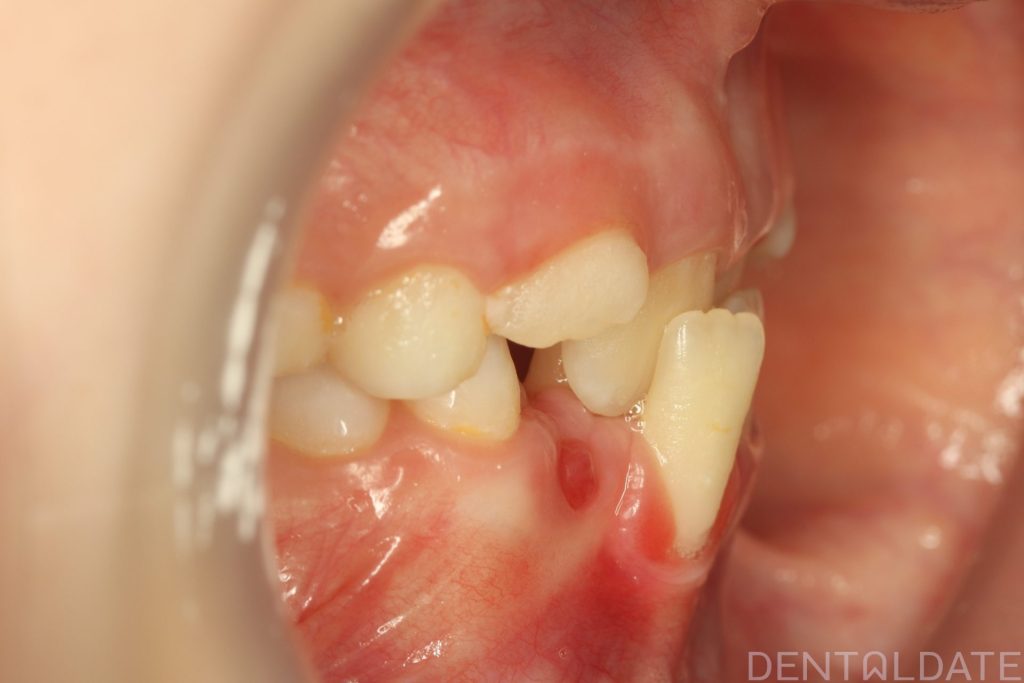

The patient had been undergoing orthodontic treatment at another clinic for 1.5 years with no significant progress.

With a new treatment plan in place -the anterior bite was normalized within just one week.

We are now focused on final adjustments to tooth alignment and occlusal height.